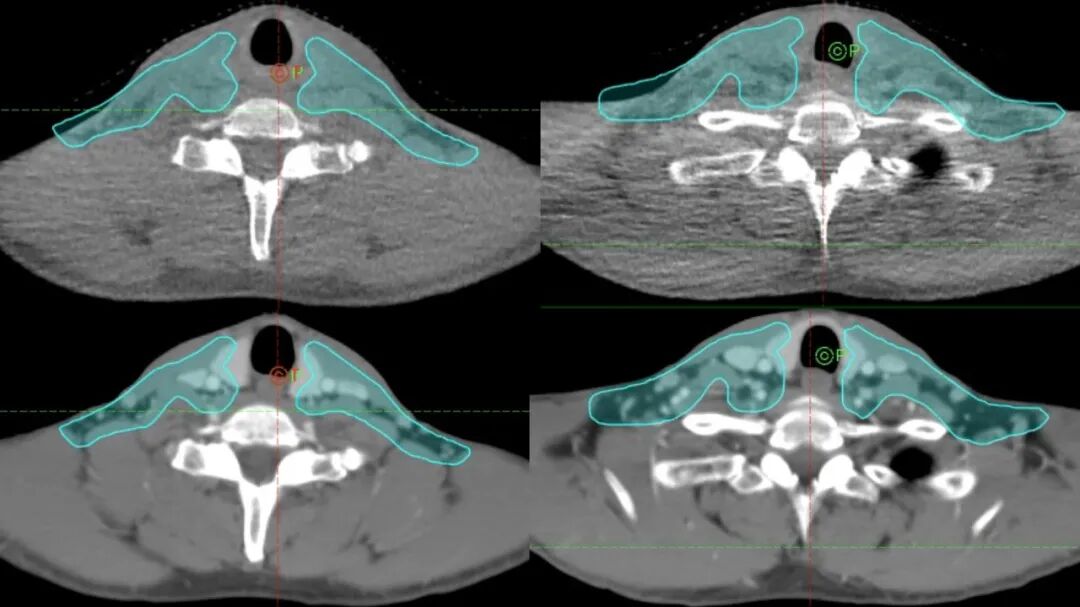

鼻咽癌放射治療需要一個(gè)半月,30余次治療。大部分患者在治療期間都會(huì)受到體重減輕,頸部形態(tài)變化等影響,進(jìn)而導(dǎo)致頸部照射區(qū)域偏離原既定計(jì)劃。Halcyon系統(tǒng)在每次放療計(jì)劃執(zhí)行前,強(qiáng)制進(jìn)行影像引導(dǎo)步驟,保證每次治療時(shí)的絕對(duì)精準(zhǔn)。如出現(xiàn)病情變化或體型改變等狀況,醫(yī)療團(tuán)隊(duì)則會(huì)及時(shí)調(diào)整放療方案,竭盡全力地為患者提供最佳的治療效果。這是全影像引導(dǎo)放療所發(fā)揮的巨大優(yōu)勢。相較傳統(tǒng)放療系統(tǒng),1~2周進(jìn)行一次影像引導(dǎo)驗(yàn)證,我們確保了每一次治療的精準(zhǔn)施照,大幅提升了腫瘤控制療效,也保證了重要組織器官的安全。

圖注:治療中掃描CBCT(錐形束計(jì)算機(jī)斷層掃描),可以發(fā)現(xiàn)因患者體型發(fā)生變化而造成的脫靶,并及時(shí)終止原計(jì)劃治療,給予患者重新定位,保證放射治療的精準(zhǔn)性。